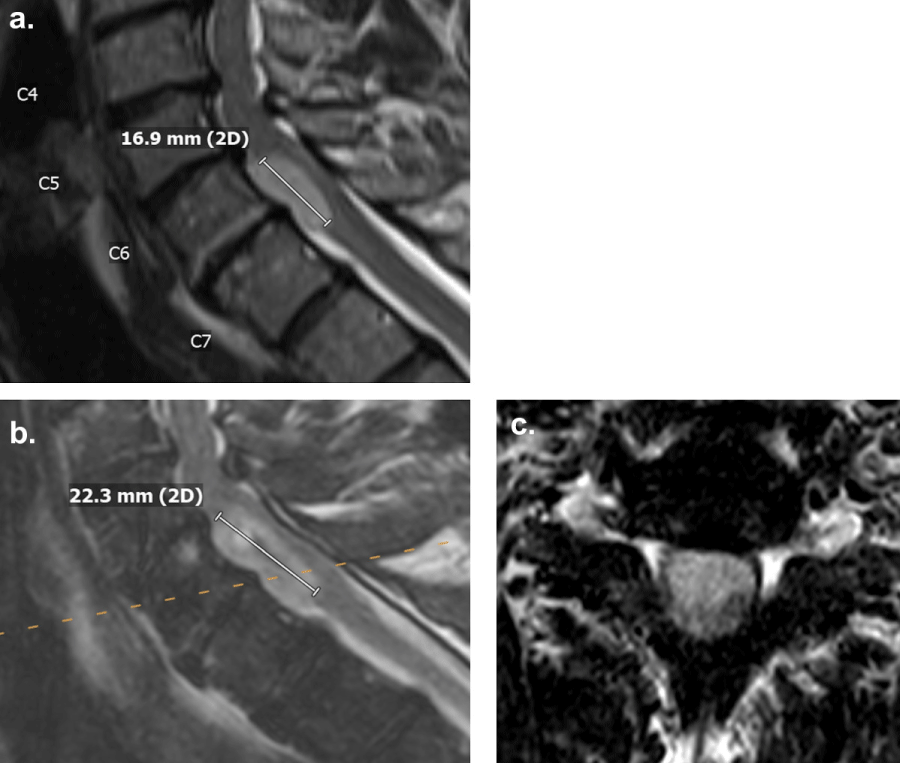

Less than two years after the sacral lesion biopsy, when the patient was 58 years old, he reported progressive weakness in his left arm and leg without numbness or tingling, though he endorsed some loss of vibration sensation in his left leg. He denied radiating pain in his extremities, saddle anesthesia, or bowel or bladder problems but reported experiencing urinary incontinence 3-4 months ago. Slight muscle weakness was observed in his left upper extremity in addition to weakness in left hip flexion and knee extension. MRI of the cervical spine revealed an intradural anterior lesion at the C6-7 level, eccentric to the left, measuring 2.2 cm in superior-inferior dimension, representing a 5.4 mm increase from the original size (Figure 2a and Figure 2b). The lesion occupied more of the spinal canal and caused a more significant mass effect on the spinal cord compared to the MRI two years prior. An open biopsy of the C6-7 lesion was proposed, as this lesion did not enhance, in contrast to the L4 and sacral lesions. It was unclear at this time whether the lesion was consistent with disseminated ependymoma. A C6-7 laminectomy was performed, and a small portion of the accessible tumor on the right side was obtained for pathology. We did not believe it was possible or safe to retract the spinal cord to attempt resection of the tumor from a posterior approach. The soft mass was consistent with low-grade ependymoma. No intraoperative or immediate postoperative complications were observed.

Figure 2: T2-weighted MRI demonstrating a hyperintense lesion without contrast enhancement at the C6-7 level anterior to the spinal cord, (a): At initial diagnosis measuring 16.9 mm in superior-inferior dimension; (b,c): Two years after initial diagnosis measuring 22.3 mm in superior-inferior dimension. View Figure 2

The patient returned to the clinic for a 1.5-month postoperative follow-up. MRI of the cervical spine taken after the biopsy continued to show a non-enhancing intradural anterior lesion at the C6-7 level, eccentric to the left. A C5-7 corpectomy for resection of the intradural extramedullary ependymoma would avoid displacement of the spinal cord, allowing for exposure of the tumor while visualizing the anterior vasculature of the spinal cord. It was also unclear whether the tumor was adherent to the anterior aspect of the spinal cord. Due to the cervical spinal cord covering nearly the entire tumor posteriorly, we did not believe a posterior approach was safe (Figure 2c). The operation was high-risk but was considered beneficial to the patient as the progressive weakness in his left upper and lower extremities would likely continue without surgical resection of the tumor. An extensive discussion was conducted with the patient and his wife, who elected to proceed with an anterior approach for cervical ependymoma resection, followed by a stage two, posterior spinal fusion, involving C2 to T3.